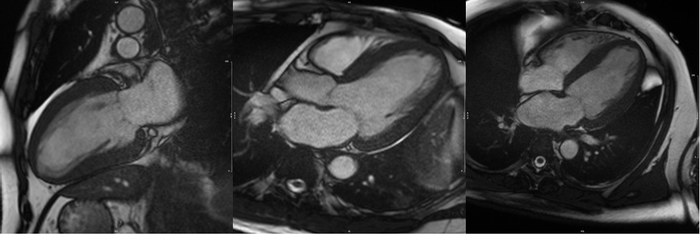

Image: CMR of a patient showing evidence of myocardial hypertrophy (thickening of heart muscles) due to hypertension.

image: Image: CMR of a patient showing evidence of myocardial hypertrophy (thickening of heart muscles) due to hypertension. view more

Credit: National Heart Centre Singapore